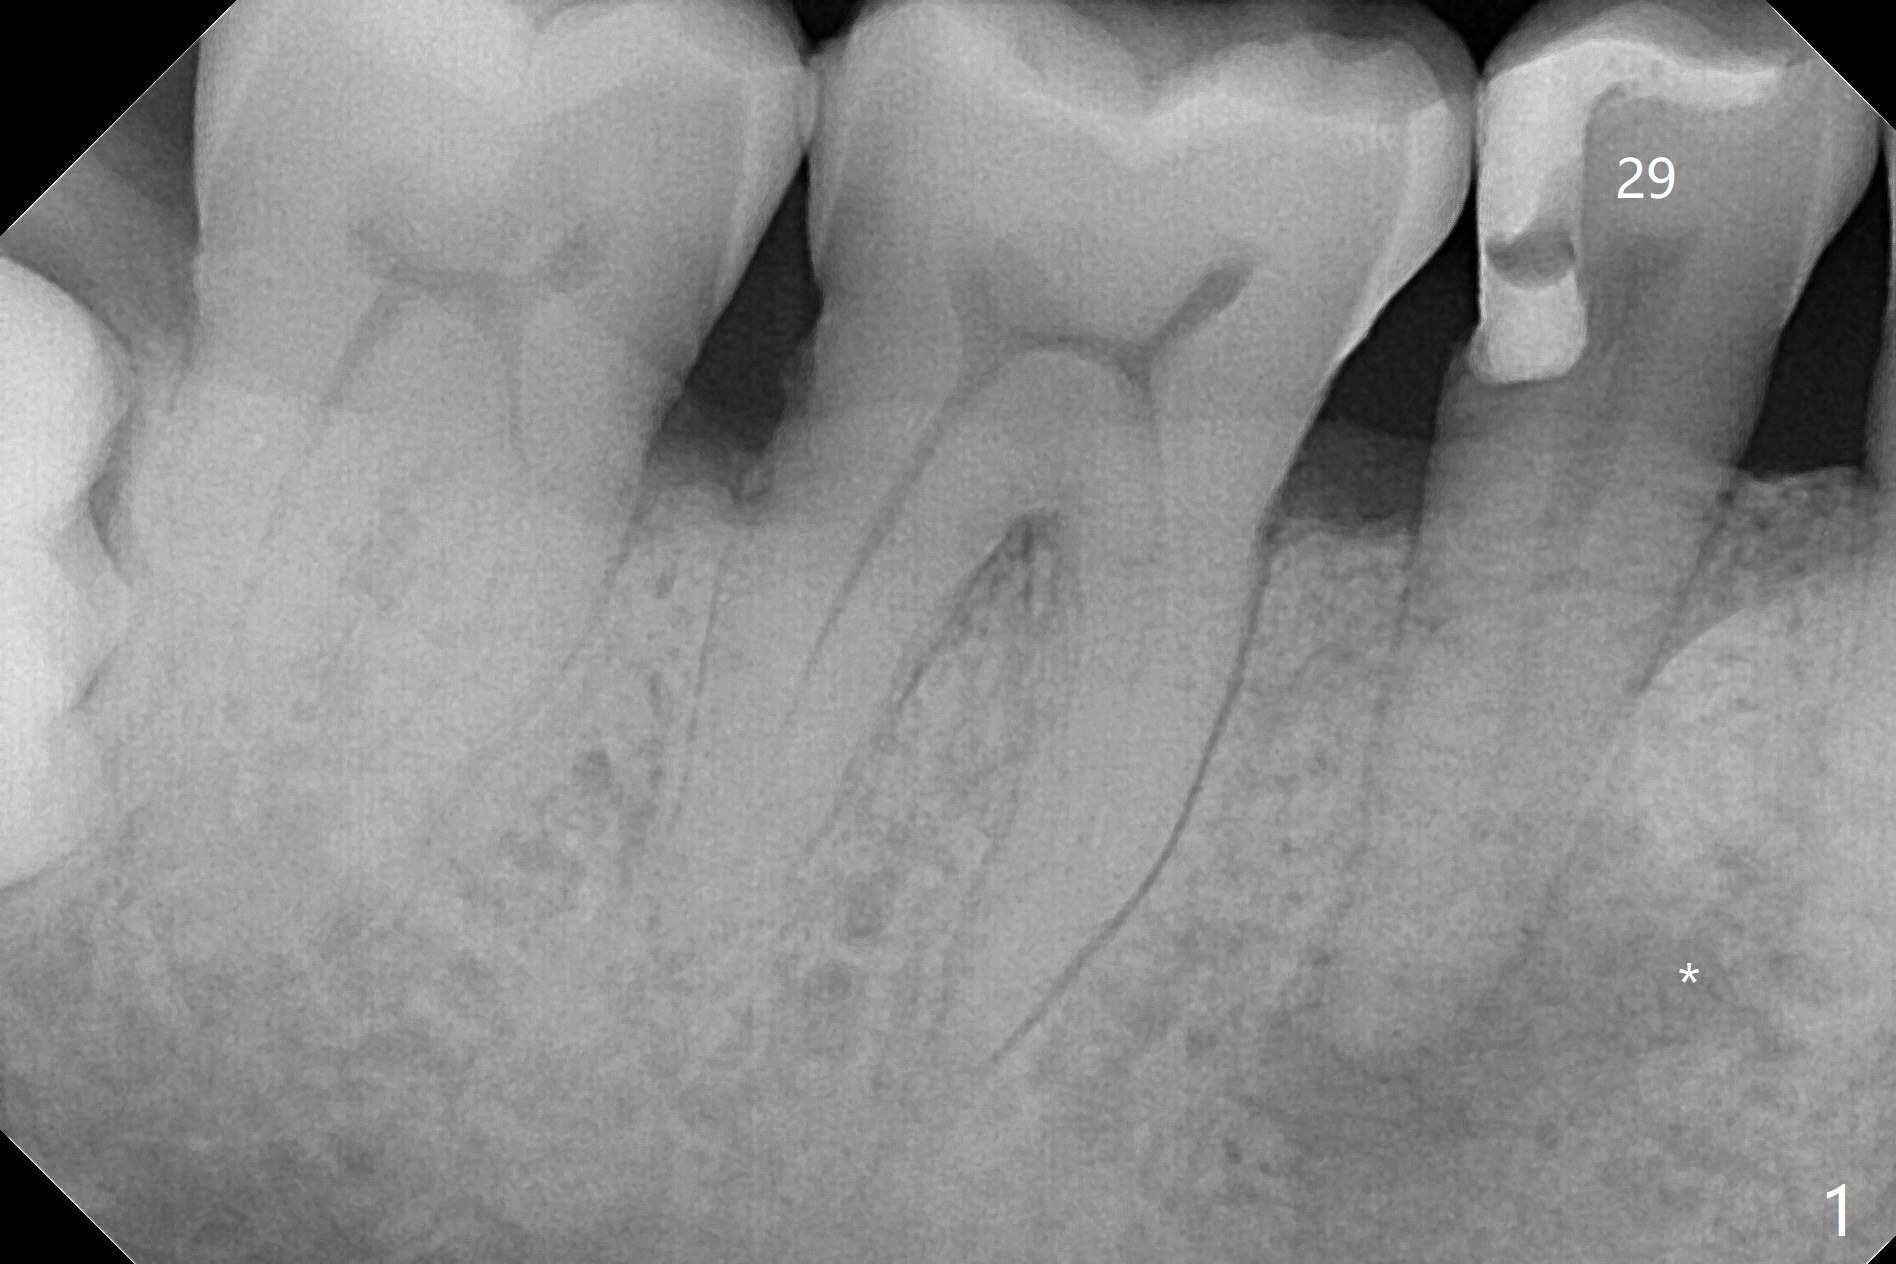

A 48-year-old man, dental phobic, wants minimal dentistry. The tooth #29 has large periapical radiolucency, extending mesial (Fig.1 *) and a fistula, apparently associated with the tooth #28 (Fig.2 *). The single canal has been debrided with 30/.06 rotary file and medicated with CaOH paste. To avoid microleakage without crown, gutta percha (Fig.3 white outline) will be cut apical to the distooclusal compostie (C). The fistula shrinks with no discharge 16 days post application of Calcium Hydroxide paste (Fig.4). RCT will be finished 2-3 weeks.